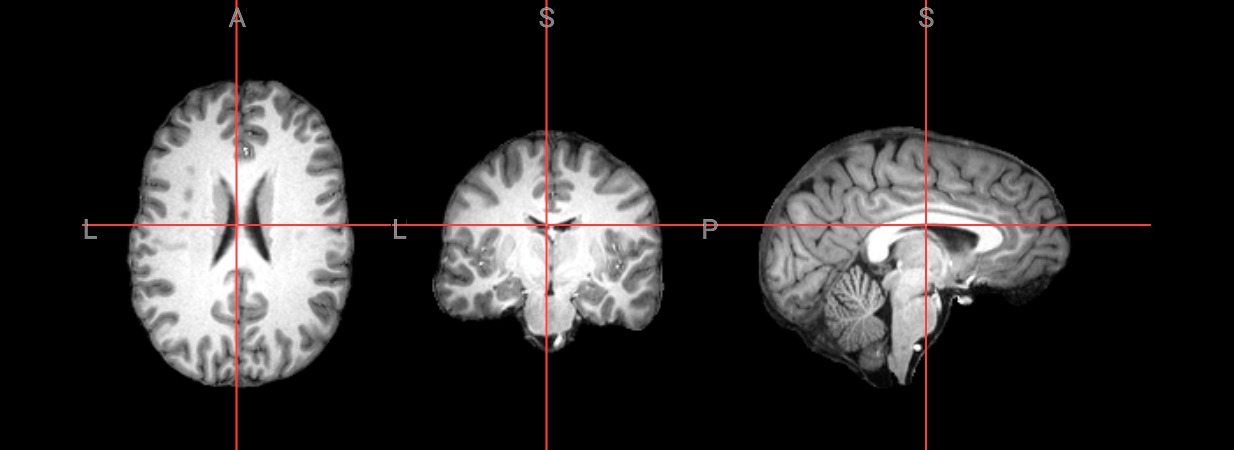

Since fMRI studies focus on brain tissue, our first step is to remove the skull and non-brain areas from the image.

T1 Image for brain extraction#